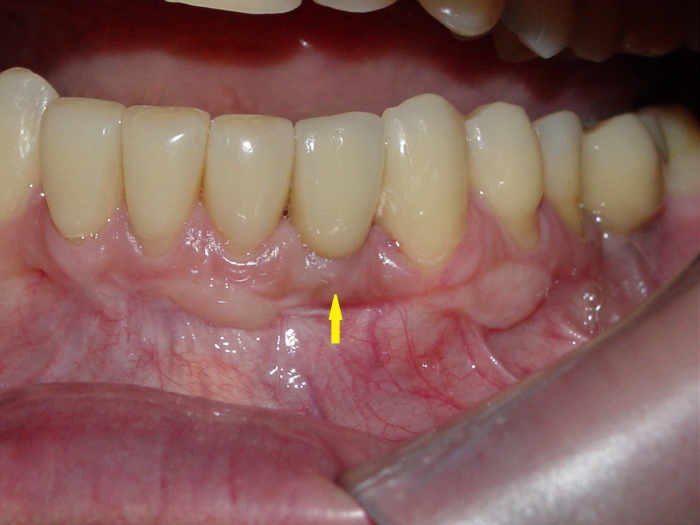

Imagem do caso finalizado em maio de 2012